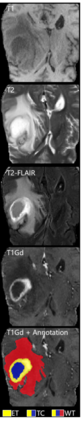

Although machine learning (ML) has shown promise in numerous domains, there are concerns about generalizability to out-of-sample data. This is currently addressed by centrally sharing ample, and importantly diverse, data from multiple sites. However, such centralization is challenging to scale (or even not feasible) due to various limitations. Federated ML (FL) provides an alternative to train accurate and generalizable ML models, by only sharing numerical model updates. Here we present findings from the largest FL study to-date, involving data from 71 healthcare institutions across 6 continents, to generate an automatic tumor boundary detector for the rare disease of glioblastoma, utilizing the largest dataset of such patients ever used in the literature (25,256 MRI scans from 6,314 patients). We demonstrate a 33% improvement over a publicly trained model to delineate the surgically targetable tumor, and 23% improvement over the tumor's entire extent. We anticipate our study to: 1) enable more studies in healthcare informed by large and diverse data, ensuring meaningful results for rare diseases and underrepresented populations, 2) facilitate further quantitative analyses for glioblastoma via performance optimization of our consensus model for eventual public release, and 3) demonstrate the effectiveness of FL at such scale and task complexity as a paradigm shift for multi-site collaborations, alleviating the need for data sharing.